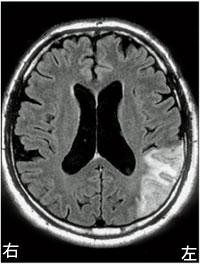

図は脳出血による左片麻痺患者の検査結果である。この結果から考えられる障害はどれか。 ...

70歳の男性。脳硬塞片麻痺、発症後2か月。図の上の絵を患者の正面に置き、模写を指示したところ、下の図のように描いた。この障害への対応として適切でないのはどれか。

72歳の男性。脳梗塞による左片麻痺。座位姿勢と机上での検査結果を図に示す。理学療法として誤っているのはどれか。

54歳の右利きの男性。脳梗塞。図のような頭部画像病変であった。みられやすい症状はどれか。